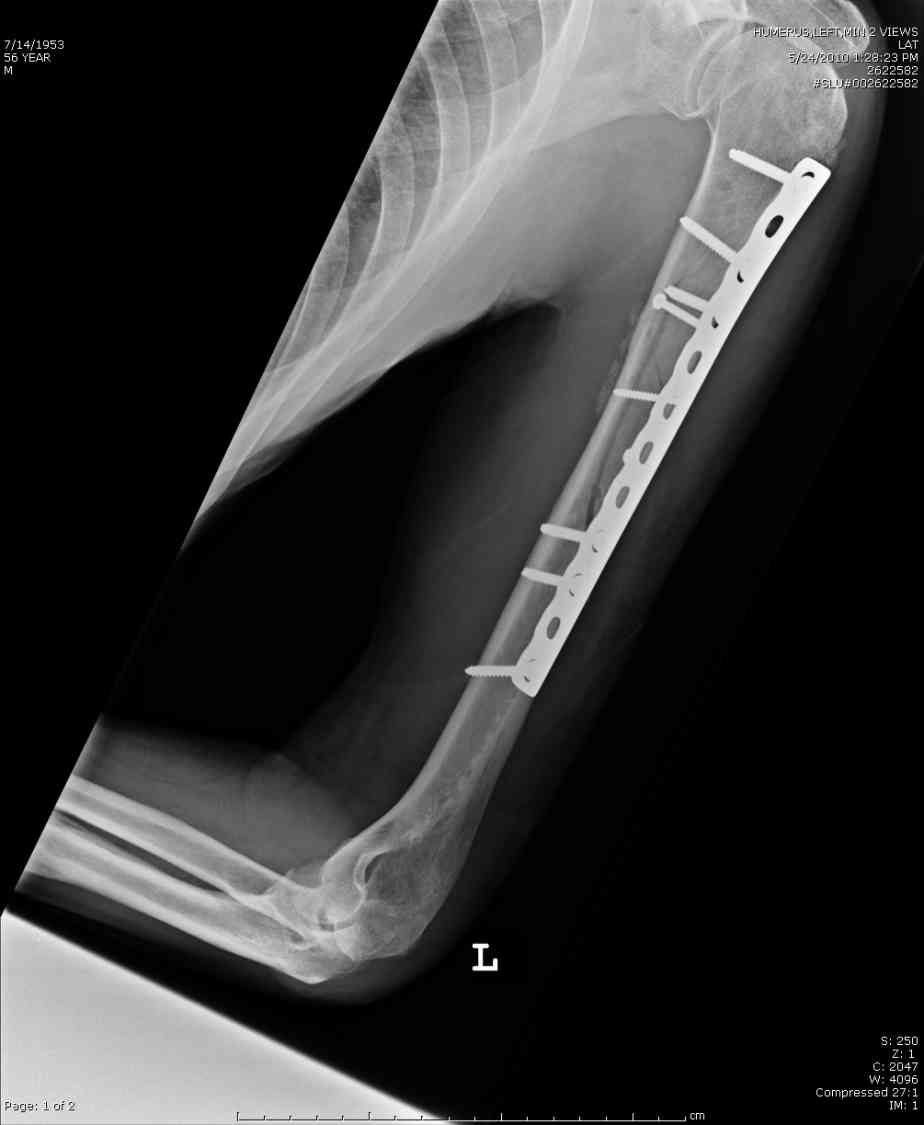

Кроме интрамедуллярного остеосинтеза, имеются другие варианты фиксации, наружный фиксатор и например здесь перелом плеча с повреждением нерва леченный открытым методом. Применен задний доступ с инспекцией нерва, межфрагментарная компрессия, фиксация узкой пластиной 4.5 мм.